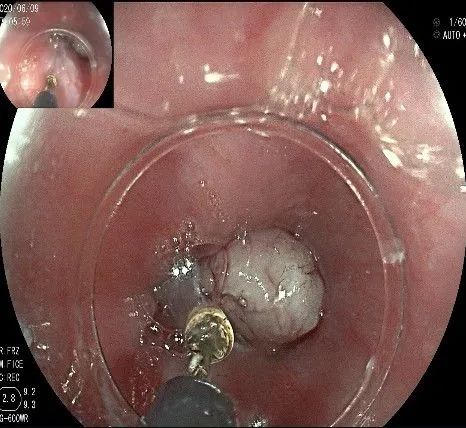

倒镜观察,可见贲门部一个明显的隆起,中央部分的凹陷,是4天前取活检留下的。

我们的思路:病变长径约2.0cm,位置活动,倒镜后先在胃底侧粘膜下注射,使病变向食管腔方向抬举,然后再在食管腔内做粘膜下注射切开,以获得一个好的术野,果然,注射后粘膜抬举明显,瘤体被挤向口侧。

在食管腔内,瘤体的两侧行粘膜下注射后,在瘤体顶部纵向自口侧向肛侧切开食管粘膜。

向下一直切开至齿状线处,白色为鳞状上皮,红色为腺上皮,颗粒样的部分,就是炎性息肉。切开后可见瘤体为白色,表面有血管网,质地较韧。